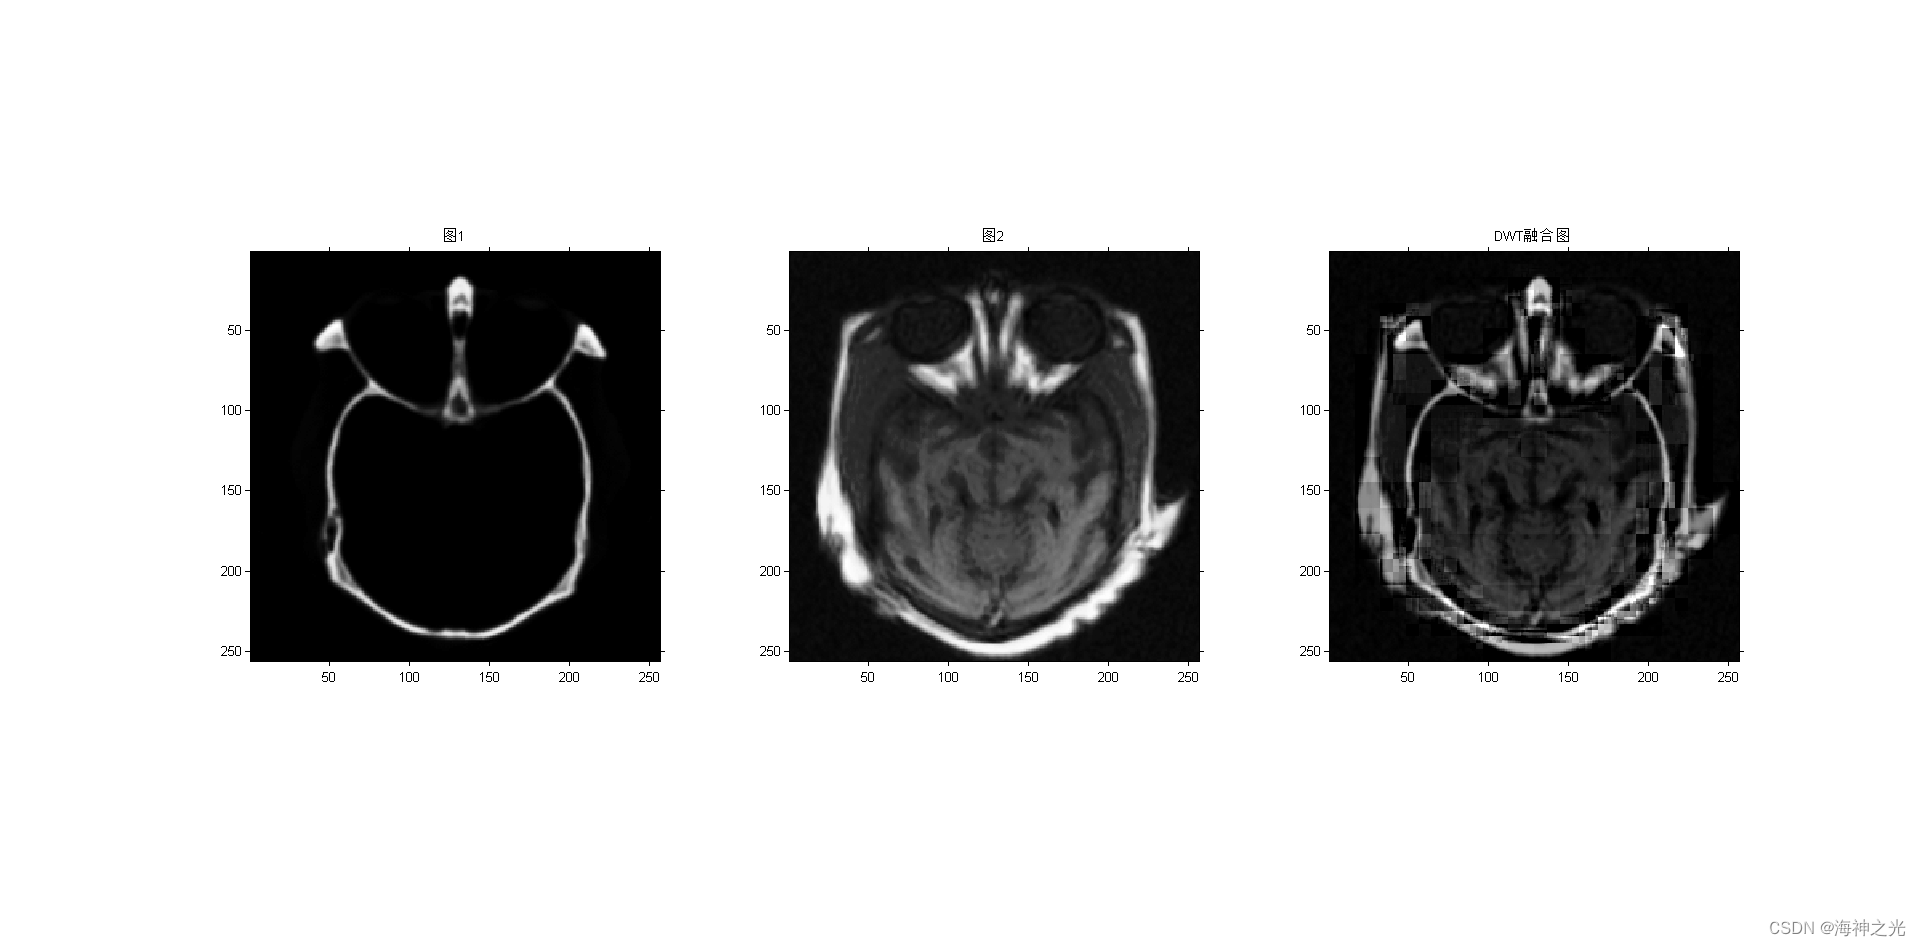

figure;subplot(131);imshow(image_input1);title(‘图1’)

subplot(132);imshow(image_input2);title(‘图2’)

subplot(133);

F = dwt_fuse(A, B, level); %DWT

title(‘DWT融合图’)

⛄三、运行结果